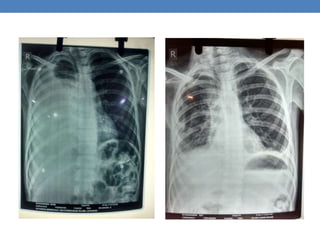

• CXR right parapnumonic effusion, CBP neutrophilic leucocytosis

• CXR increased right parapnumonic effusion, ICD placed, serial CXR no

• Evaluated for TB, CXR right pneumothorax, ESR 110, Sputum AFB